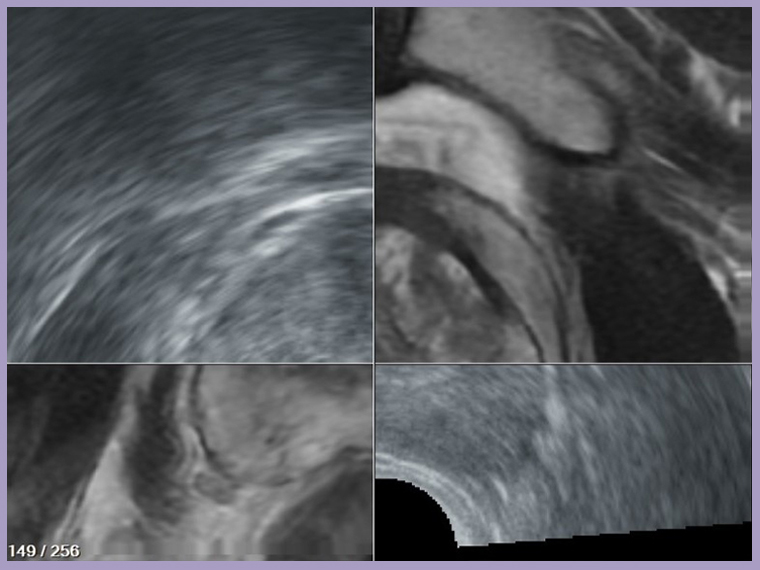

【NOW健康 楊芷晴/新北報導】79歲黃先生多年受攝護腺肥大困擾,出現排尿困難與夜尿頻繁等症狀。2018年初診時,其攝護腺特異抗原(PSA)達8.8ng/mL(正常值≤4ng/mL),但透過傳統經直腸超音波導引切片後為良性,因此並未進一步追蹤。2022年因不適再度至台北慈濟醫院泌尿科就診,PSA再度升高至10ng/mL,進一步安排核磁共振(MRI)檢查,發現多處疑似病灶。台北慈濟醫院泌尿科鐘伯恩醫師運用軟體技術,將MRI與即時超音波影像融合,精準導引切片至高風險區域,最終確診早期攝護腺癌,黃先生順利接受達文西機械臂輔助手術切除,術後2年追蹤均無復發。

▲將MRI與即時超音波影像融合。(圖/台北慈濟醫院提供)

傳統經直腸隨機切片方式猶如「盲抽」,可能誤判為良性或需重複切片。MRI雖能判讀可疑病灶,卻難以即時定位;超音波則無法準確辨認病灶,因此最適切的診斷方式是將2種影像融合後,進行導引切片。台北慈濟醫院泌尿科團隊導入軟體輔助影像融合切片技術,先由MRI標記病灶,再於即時超音波中進行影像疊合與校準,鎖定病灶進行經會陰切片,大幅提升精準度,並因避開直腸入針,大幅降低感染與敗血症風險,惟檢查時需全身麻醉。